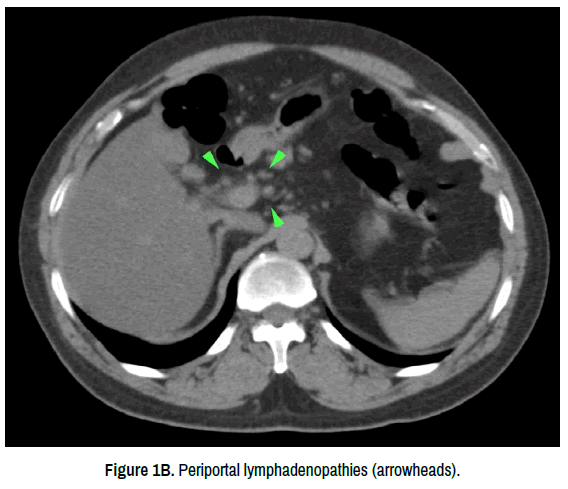

There were no pathological findings in the physical examinations of the patients during admission. The patient with fulminant hepatitis was followed up in the intensive care unit, and the other five stable patients were followed up in the inpatient ward. The current hepatitis tables were evaluated as the hepatocellular pattern. Intravenous (i.v.) hydration and acetylcysteine 3x1 ampule iv. were administered to the patients. Two sessions of plasmapheresis were performed in the case of the patient who had fulminant hepatitis. HBs Ag, HBV Ig-M, HAV Ig-M, Anti-HCV, HEV Ig-M, ANA, AMA, ASMA, serum Ig G-A-M were negative. There was no history of comorbidity, alcohol, illicit drug or medication use, and no evidence of heart failure. General characteristics and laboratory findings of patients at presentation are shown in Table 1. In all abdominal USG’s of the patients, liver size growth and peri-portal edema were observed. Axial non-contrast-enhanced CT slices show diffusely decreased parenchymal attenuation (low hepatic HU values compared to the spleen) (A) and periportal lymphadenopathies (arrowheads)(B) (Figure 1A & 1B). An improvement was observed in the clinical presentation of the patients and their laboratory findings during follow-ups. Patients were discharged after a mean follow-up of five days. Elevation of the patients’ liver function tests completely resolved in an average of one month. Informed consent was obtained from the patients for the publication of health records.

Figure 1b. Periportal lymphadenopathies (arrowheads).